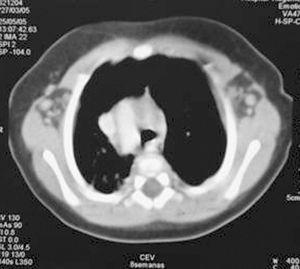

Analítica: hipocalcemia (calcio 5,8 mg/dl, calcio iónico 2,9 mg/dl), proteínas totales 6,1 g/dl, y albúmina 3,3 g/dl. Se descarta déficit de vitamina D (25[OH]D 11 ng/ml), hipomagnesemia (Mg de 1,4 mg/dl), ingesta elevada de fósforo (no constatada), causas yatrogénicas o alcalosis (pH 7,33 con bicarbonato de 21 mmol/l). El valor de PTH es bajo (16,1 ng/ml). En la radiografía de tórax se observa arco aórtico derecho y aplasia tímica (fig. 1), confirmadas en la TC torácica superior (fig. 2). Diagnóstico de hipocalcemia secundaria a hipoparatiroidismo congénito, incluido dentro del síndrome de DiGeorge. Cariotipo 46XX. FISH: microdeleción 22q11- (D22s75-).

Figura 2.TC torácica superior: arco aórtico derecho. Ausencia de timo.

El inicio clínico de nuestra paciente, consiste en crisis convulsivas debidas a la hipocalcemia secundaria a hipoparatiroidismo congénito, habiéndose descartado debidamente otras etiologías. El hipoparatiroidismo congénito puede deberse a mutaciones en los genes de la PTH, a mutaciones activas en el receptor sensor del calcio (CASR)3, a la agenesia de las glándulas paratiroides, a síndromes metabólicos, o al síndrome de DiGeorge. La ecografía cervical y TC torácica superior realizados revelan ausencia de timo y arco aórtico derecho asociado; todo ello sugestivo de síndrome de DiGeorge4.